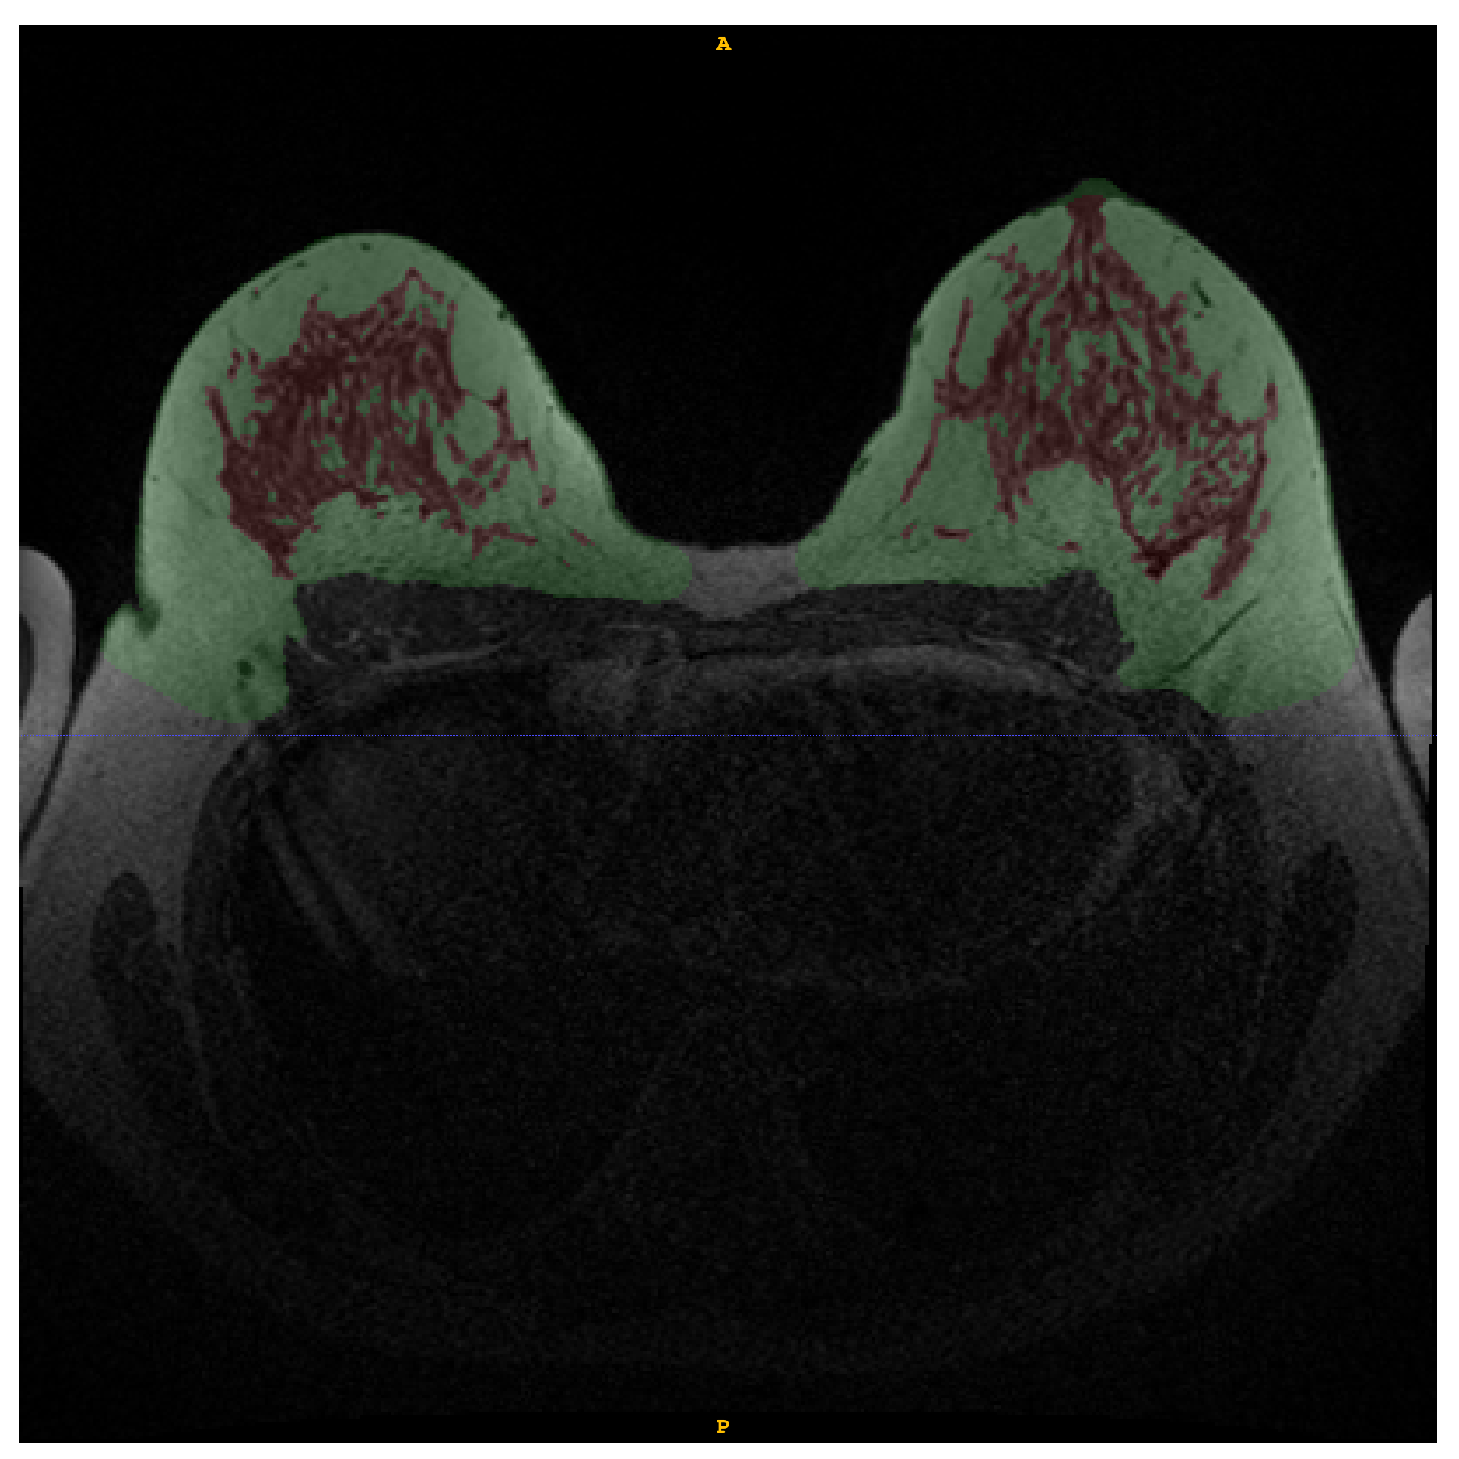

Figure 2. Example of manual annotation of fat tissue (green) and FGT (red) in WOFS image.

The breast and FGT regions were manually annotated by R.S. under the supervision of an experienced breast radiologist (with 16 years of experience) using the software ITKSNAP [15]. The breast fat tissue and FGT regions were manually annotated using the WOFS image—see Figure 2—and, when in doubt about boundaries for either breast fat tissue or FGT areas, also the FS image was consulted. The exact same segmentation could be used for WOFS and FS acquisitions without the need of registration.